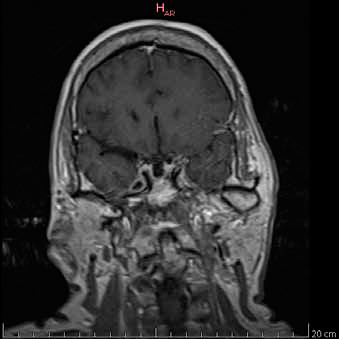

En exámenes de laboratorio se obtuvieron los siguientes resultados: IGF-1 372 ng/ml (69 - 200 ng/mL); prueba de tolerancia oral a la glucosa midiendo GH (PTG-GH): 0 minutos - 2,14/ 30 minutos - 1,38/ 60 minutos - 1,49/ 90 minutos - 1,52/ 120 minutos - 1,52/ 150 minutos - 1,55/ 180 minutos - 1,21 ng/ml; TSH: 1.28 ulU/ml (0.4 - 4 ulU/ml); prolactina: 5.2 ng/ mL (1.9 - 25 ng/mL). Los estudios de imagen informaron: RMN (Resonancia magnética nuclear) de hipófisis región selar parcialmente llena de líquido cefalorraquídeo (LCR) con dificultad para identificar el tejido hipofisario, herniación de aracnoides y el LCR que comprime a la glándula contra el suelo selar; tras la administración de contraste solo se aprecia refuerzo del infundíbulo, tallo hipofisario en línea media de aspecto normal, quiasma óptico de características normales, estructura hipotalámica normal, asimetría en la relación de los diámetros mayores entre el macizo cráneo facial y la bóveda craneal (Figura 1a y 1b). En Radiografía (Rx) columna: Rotoescoliosis, acentuación de la lordosis lumbar, disminución de espacios discales lumbares. Rx rodilla: prominencia de las espinas tibiales medial y lateral, disminución del espacio interarticular femoropatelar y femorotibial interno, osteofitos en cóndilo femoral y tibial. Rx de mano: erosiones óseas marginales, estrechamiento de los espacios interfalangicos.

Figura 1a. RMN de silla turca contrastada con gadolinio. Corte sagital en T1. Cortes 2.5 mm. Se señala región selar.

Figura 1b. RMN de silla turca contrastada con gadolinio. Corte coronal en T1. Cortes 2.5 mm.